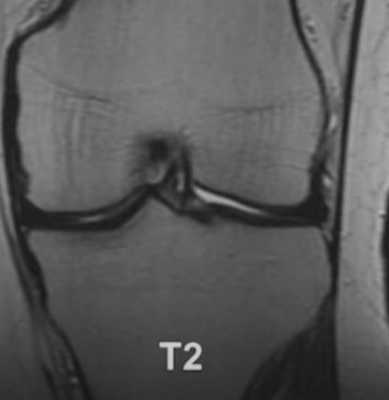

На МРТ хорошо прослеживаются все стадии этого процесса. На томограмме определяется выпот синовиальной жидкости и подхрящевая костная киста при остеоартрозе коленного сустава.

Фронтальный срез МРТ коленного сустава